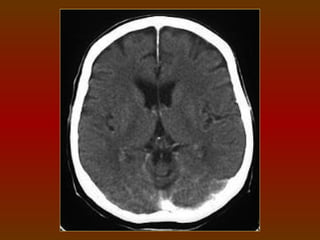

CORTE 5

a) Lobo frontal

b) Corno frontal do ventrículo lateral

c) Fissura silviana

d) Terceiro ventrículo

e) Glândula pineal (calcificada)

f) Plexo coróide (calcificado)

g) Lobo occipital